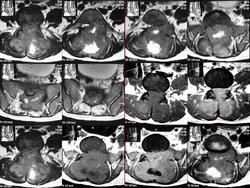

Гигантоклеточная опухоль.

1.gko_.slayd149.jpg2.gko_.slayd150.jpg3.gko_.slayd151.jpg4.gko_.slayd152.jpg